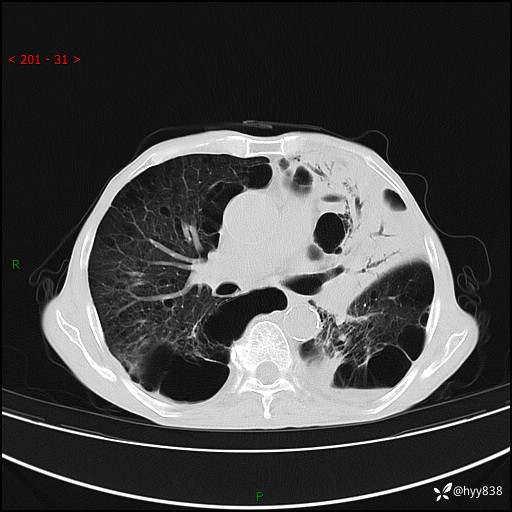

老年男性,反复咳嗽、咳痰、气喘10余年,再发3天。大叶性实变+胸膜病变-结果公布

主诉:反复咳嗽、咳痰、气喘10余年,再发3天

现病史:患者于10余年前开始出现反复咳嗽,咳痰,偶有少许黄色粘痰,伴活动后气喘,多于受凉及天气变化时发作,无胸痛、心悸、咯血等症状,休息后可自行缓解,起初因症状轻微可耐受,未到医院诊治,后症状逐渐加重,频发活动后气喘,活动耐力逐渐下降,未予药物治疗。3天前患者腹泻后出现气喘加重,伴咳嗽,咳黄色粘痰,痰较多,不易咳出,食欲差,无发热,无头昏、乏力、心慌,无头痛、晕厥,无端坐呼吸,无咯血,无胸痛、腹痛,无下肢水肿等,为求进一步诊治,来我院,急诊以“慢性阻塞性肺疾病伴急性下呼吸道感染”收入我科。 本次急性发作以来,患者精神、食欲差,大小便如常,体力下降。体重无明显变化。

胸部CT平扫+增强